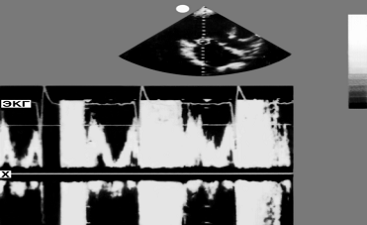

Рис. 5. Нормальная эхокардиограмма в М-режиме и допплер-эхокардиограмма - спектрограмма потока крови (внизу) в полости левого предсердия вблизи створок митрального клапана (локация со стороны левого желудочка). На спектрограмме представлен ламинарный (нормальный) поток через митральный клапан в диастолу. Сигналы имеют светлое "окно" в середине (указано стрелками), что свидетельствует о ламинарном потоке, и располагаются выше изолинии (х), что указывает направление потока в сторону датчика

Цикл, в котором зарегистрирована эхокардиограмма. Справа вверху - шкала акустической плотности в оптическом выражении">